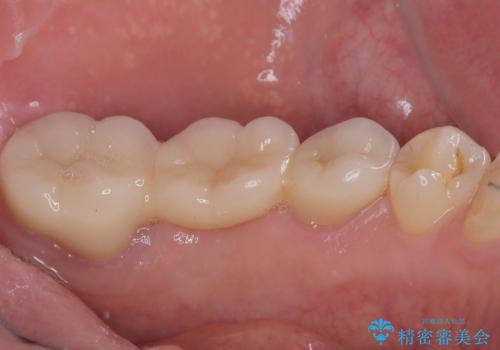

まずは奥歯の痛みを改善し、その後矯正治療を行い、最後にオールセラミックブリッジによる補綴治療を行うこととしました。

むし歯をきっかけに矯正治療を行うこととなりましたが、学生の頃から気になっていた歯列を改善することができ、患者様には大変満足していただけました。